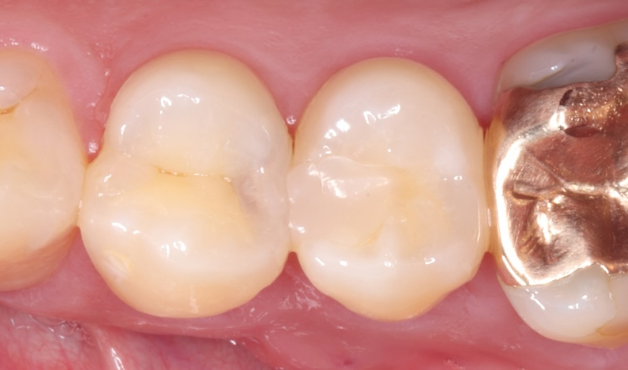

長期予後を見越した根管治療の症例

タップで写真の拡大ができます。

Before

After

主訴

症状はないが、治療が必要な箇所があればしっかり治療しておきたい。

治療内容

イニシャルトリートメント(根管治療・大臼歯)、ファイバーポストコア、セラミッククラウン

治療期間

3ヶ月

治療費用

352,000

治療の

リスク

根尖部透過像が完全に消失しない可能性があります。